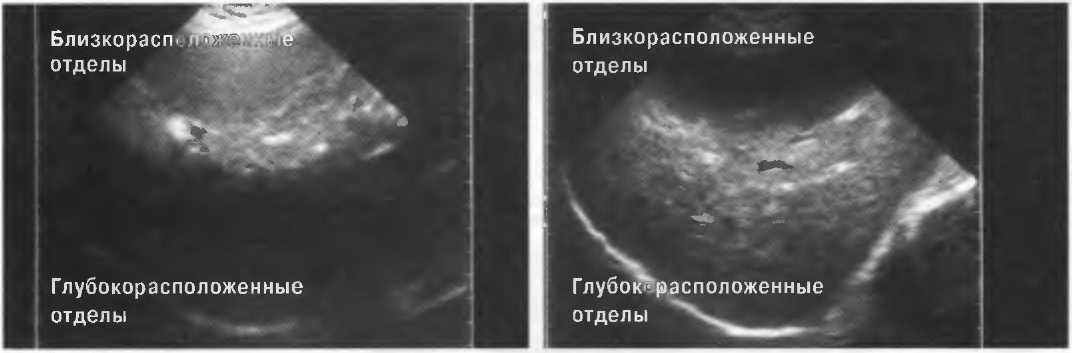

Усиление

Эхосигналы, отраженные от глубокорасположенных структур, являются более слабыми, чем те, которые идут от поверхностных структур; поэтому они должны быть усилены. В ультразвуковом аппарате есть устройство, компенсирующее затухание эхосигнала по глубине. Во всех ультразвуковых сканерах есть возможность изменять степень усиления и улучшать качество получаемого изображения (рис. 4).

Рис.4. На эхограмме слева усиление глубоких тканей слабое, поэтому от них нет отраженных сигналов. На правой эхограмме произведена коррекция чувствительности, и отраженные сигналы имеют одинаковую интенсивность по всей глубине.

Чувствительность и регулировка чувствительности прибора

Необходимо знать, что неправильная регулировка чувствительности может сделать диагностику неточной либо просто невозможной.

На эхограммах рис. 13 представлены различные варианты регулировки чувствительности и усиления по глубине.

Рис. 13а. Эхография печени. Слева: слишком слабое усиление глубоких отделов. Справа: слишком слабое усиление поверхностных отделов.